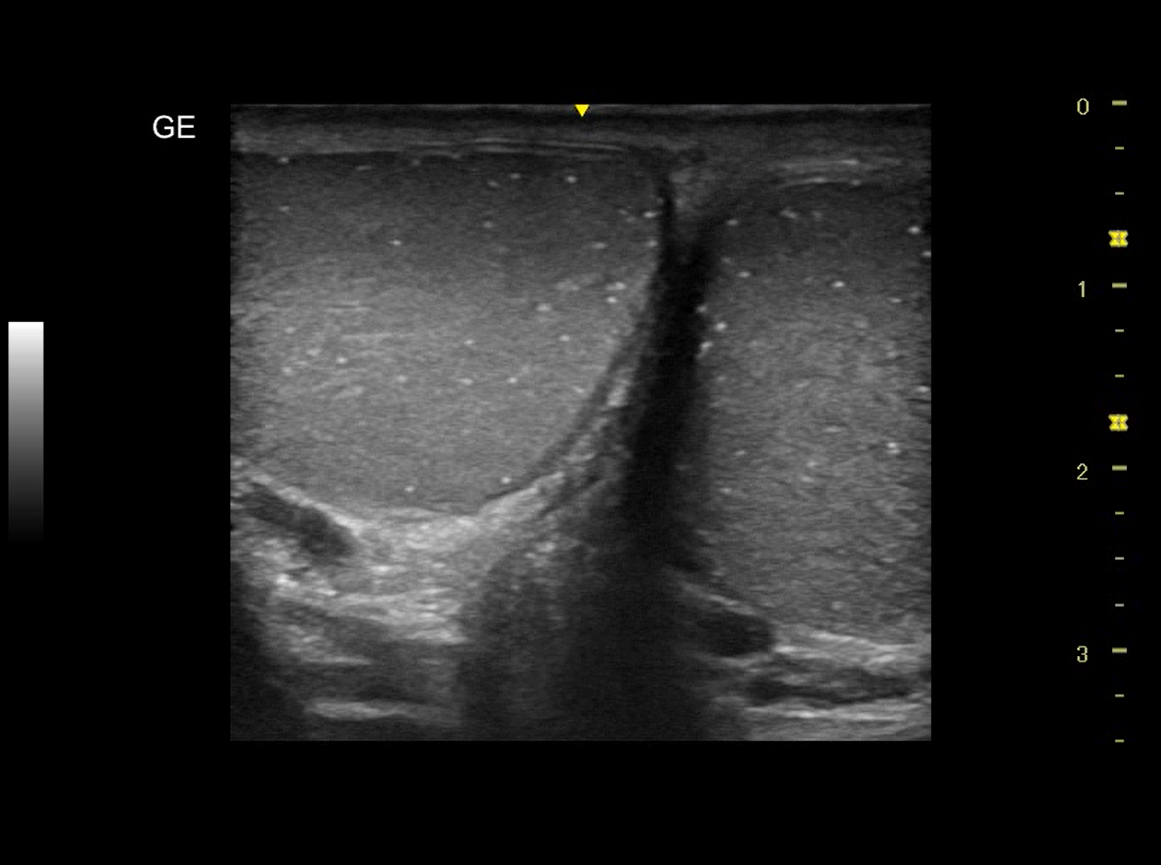

Realizamos ecografía clínica testicular: observamos ambos testículos con microlitiasis bilaterales puntiforme sin sombras acústicasen, en forma de cielo estrellado, vascularización normal, cabeza epidídimo izquierdo con leves signos inflamatorios, mínimo hidrocele.

Microlitisis testicular bilateral en contexto de Orquiepidimitis aguda. Diagnóstico diferencial con tumor testicular, torsión testicular, absceso testicular, hidátide.